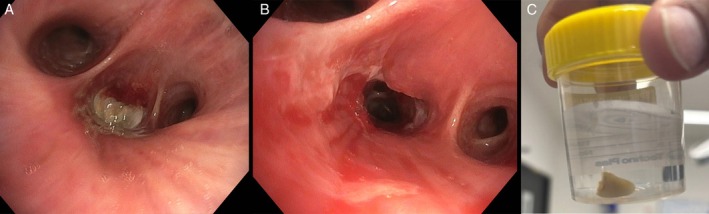

A Crumpet, a Canine and a Cryoprobe: A Case of Tooth Aspiration.

Foreign body inhalation can lead to post-obstructive pneumonia and sepsis, requiring timely removal to achieve source control. We report a case of tooth aspiration successfully retrieved with a cryoprobe.